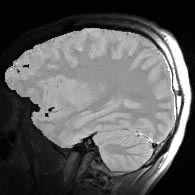

| + | {| | ||

| + | |+ '''Fig 4. Surface Coil EM Segmentations(1995)''' | ||

| + | |valign="top"|[[Image:nine.jpg|thumb|252px|surface coil image]] | ||

| + | |valign="top"|[[Image:ten.jpg|thumb|252px|surface coil image corrected by EM algorithm]] | ||

| + | |} | ||

The EM segmenter proved to be very robust to shading artifacts, but in addition, it was also robust to "inter-scan inhomogeneities". With previous classification approaches to segmentation, "training" was needed on a per-scan basis, because of intensity changes from scan to scan.

The EM segmener was the first algorithm that could produce high quality segmentations of white matter and gray matter from MRI, with no manual intervention needed on a per case basis. This proved to be very valuable in a large longitudinal study of MS in the period 1994 - 1995.